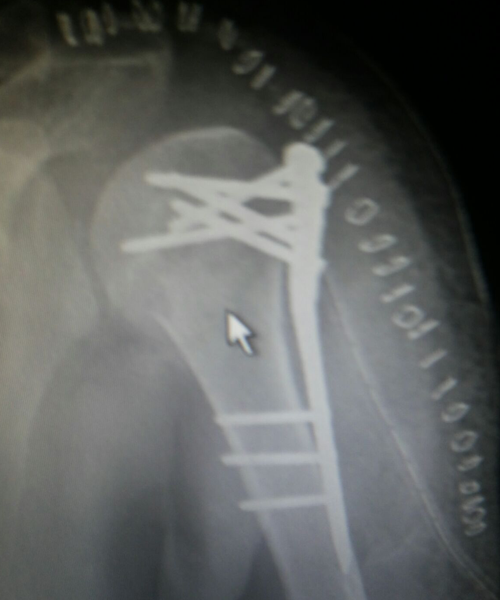

Case:7 Fracture Neck Femur with Implant failure and Re-Fixation with hemi-arthroplasty

Alcoholic Gardener by profession had slipped in bathroom & fell. He sustained fracture neck femur.He was operated with closed reduction & CC Screw fixation under IITV. Two weeks’ post fixation he again fell & sustained fracture in sub trochanteric region. He was treated with Hem-Arthroplasty with Tension band wiring.

Pre-Op

Post-Op

Post Fall

Oblique-Post Fall